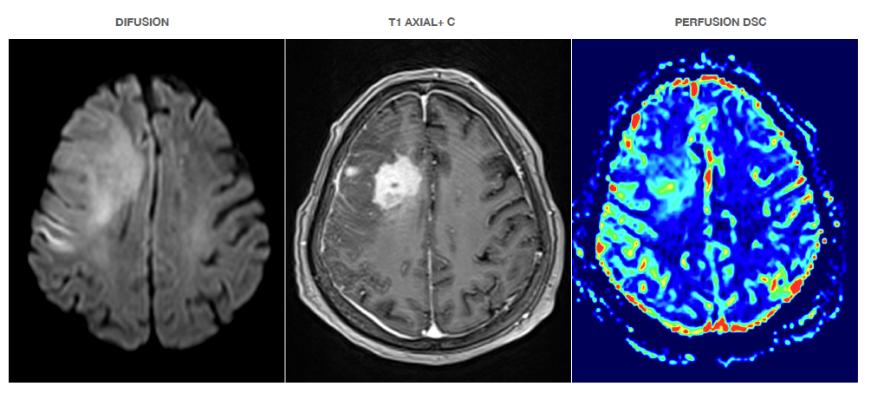

La re-publicación de artículos de la RIIS debe hacer referencia a la publicación inicial y, si se comparte en formatos digitales, enlazar a artículos originales al sito de la revista para proporcionar a los lectores acceso a cualquier corrección, correspondencia relacionada y características digitales.

Conflictos de intereses y divulgaciones financieras

La RIIS solamente publica investigaciones confiables y autorizadas que estén libres de influencias comerciales; para ello, se solicita que los autores listen las fuentes de financiamiento que patrocinaron el trabajo; por otro lado ninguno de los editores de la RIIS tiene relación comercial con ninguna empresa biomédica.

Manipulación de Figuras

Para todo manuscrito, los autores deben describir e indicar claramente todas las modificaciones, ajustes digitales selectivos y mejoras electrónicas realizadas a cualquier imagen digital; los autores también deben asegurarse de que todas las figuras enviadas cumplan con los siguientes criterios:

• No se ha mejorado, oscurecido, movido, eliminado o introducido ninguna característica específica en una imagen.

• Cualquier ajuste de brillo, color o contraste se ha realizado en una imagen completa y no tergiversa ninguna característica de la imagen original.

• No se ha duplicado ninguna imagen en el manuscrito ni se ha publicado en otro lugar.

• Los metadatos de la imagen original están disponibles y se pueden proporcionar a los editores de la RIIS a solicitud.